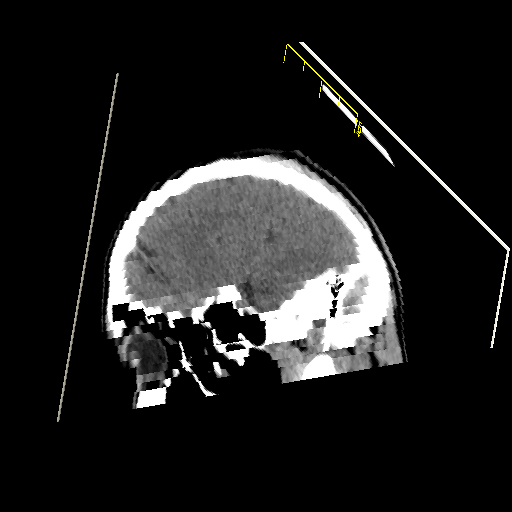

To start with, the program can be used to take slices of the 3D volume from any angle and position. The following is an example of a diagonal slice from the corner

Diagonal slice of 3D volume formed by stacked MRI images.